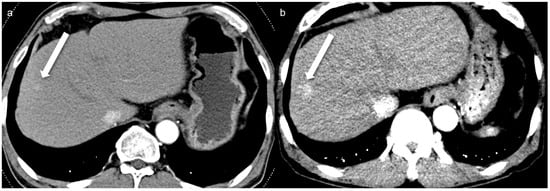

- Yoon, J.H.; Chang, W.; Lee, E.S.; Lee, S.M.; Lee, J.M. Double Low-Dose Dual-Energy Liver CT in Patients at High-Risk of HCC: A Prospective, Randomized, Single-Center Study. Investig. Radiol. 2020, 55, 340–348. [Google Scholar] [CrossRef] [PubMed]

- Yoon, J.H.; Park, J.Y.; Lee, S.M.; Lee, E.S.; Kim, J.H.; Lee, J.M. Renal protection CT protocol using low-dose and low-concentration iodine contrast medium in at-risk patients of HCC and with chronic kidney disease: A randomized controlled non-inferiority trial. Cancer Imaging 2023, 23, 100. [Google Scholar] [CrossRef]